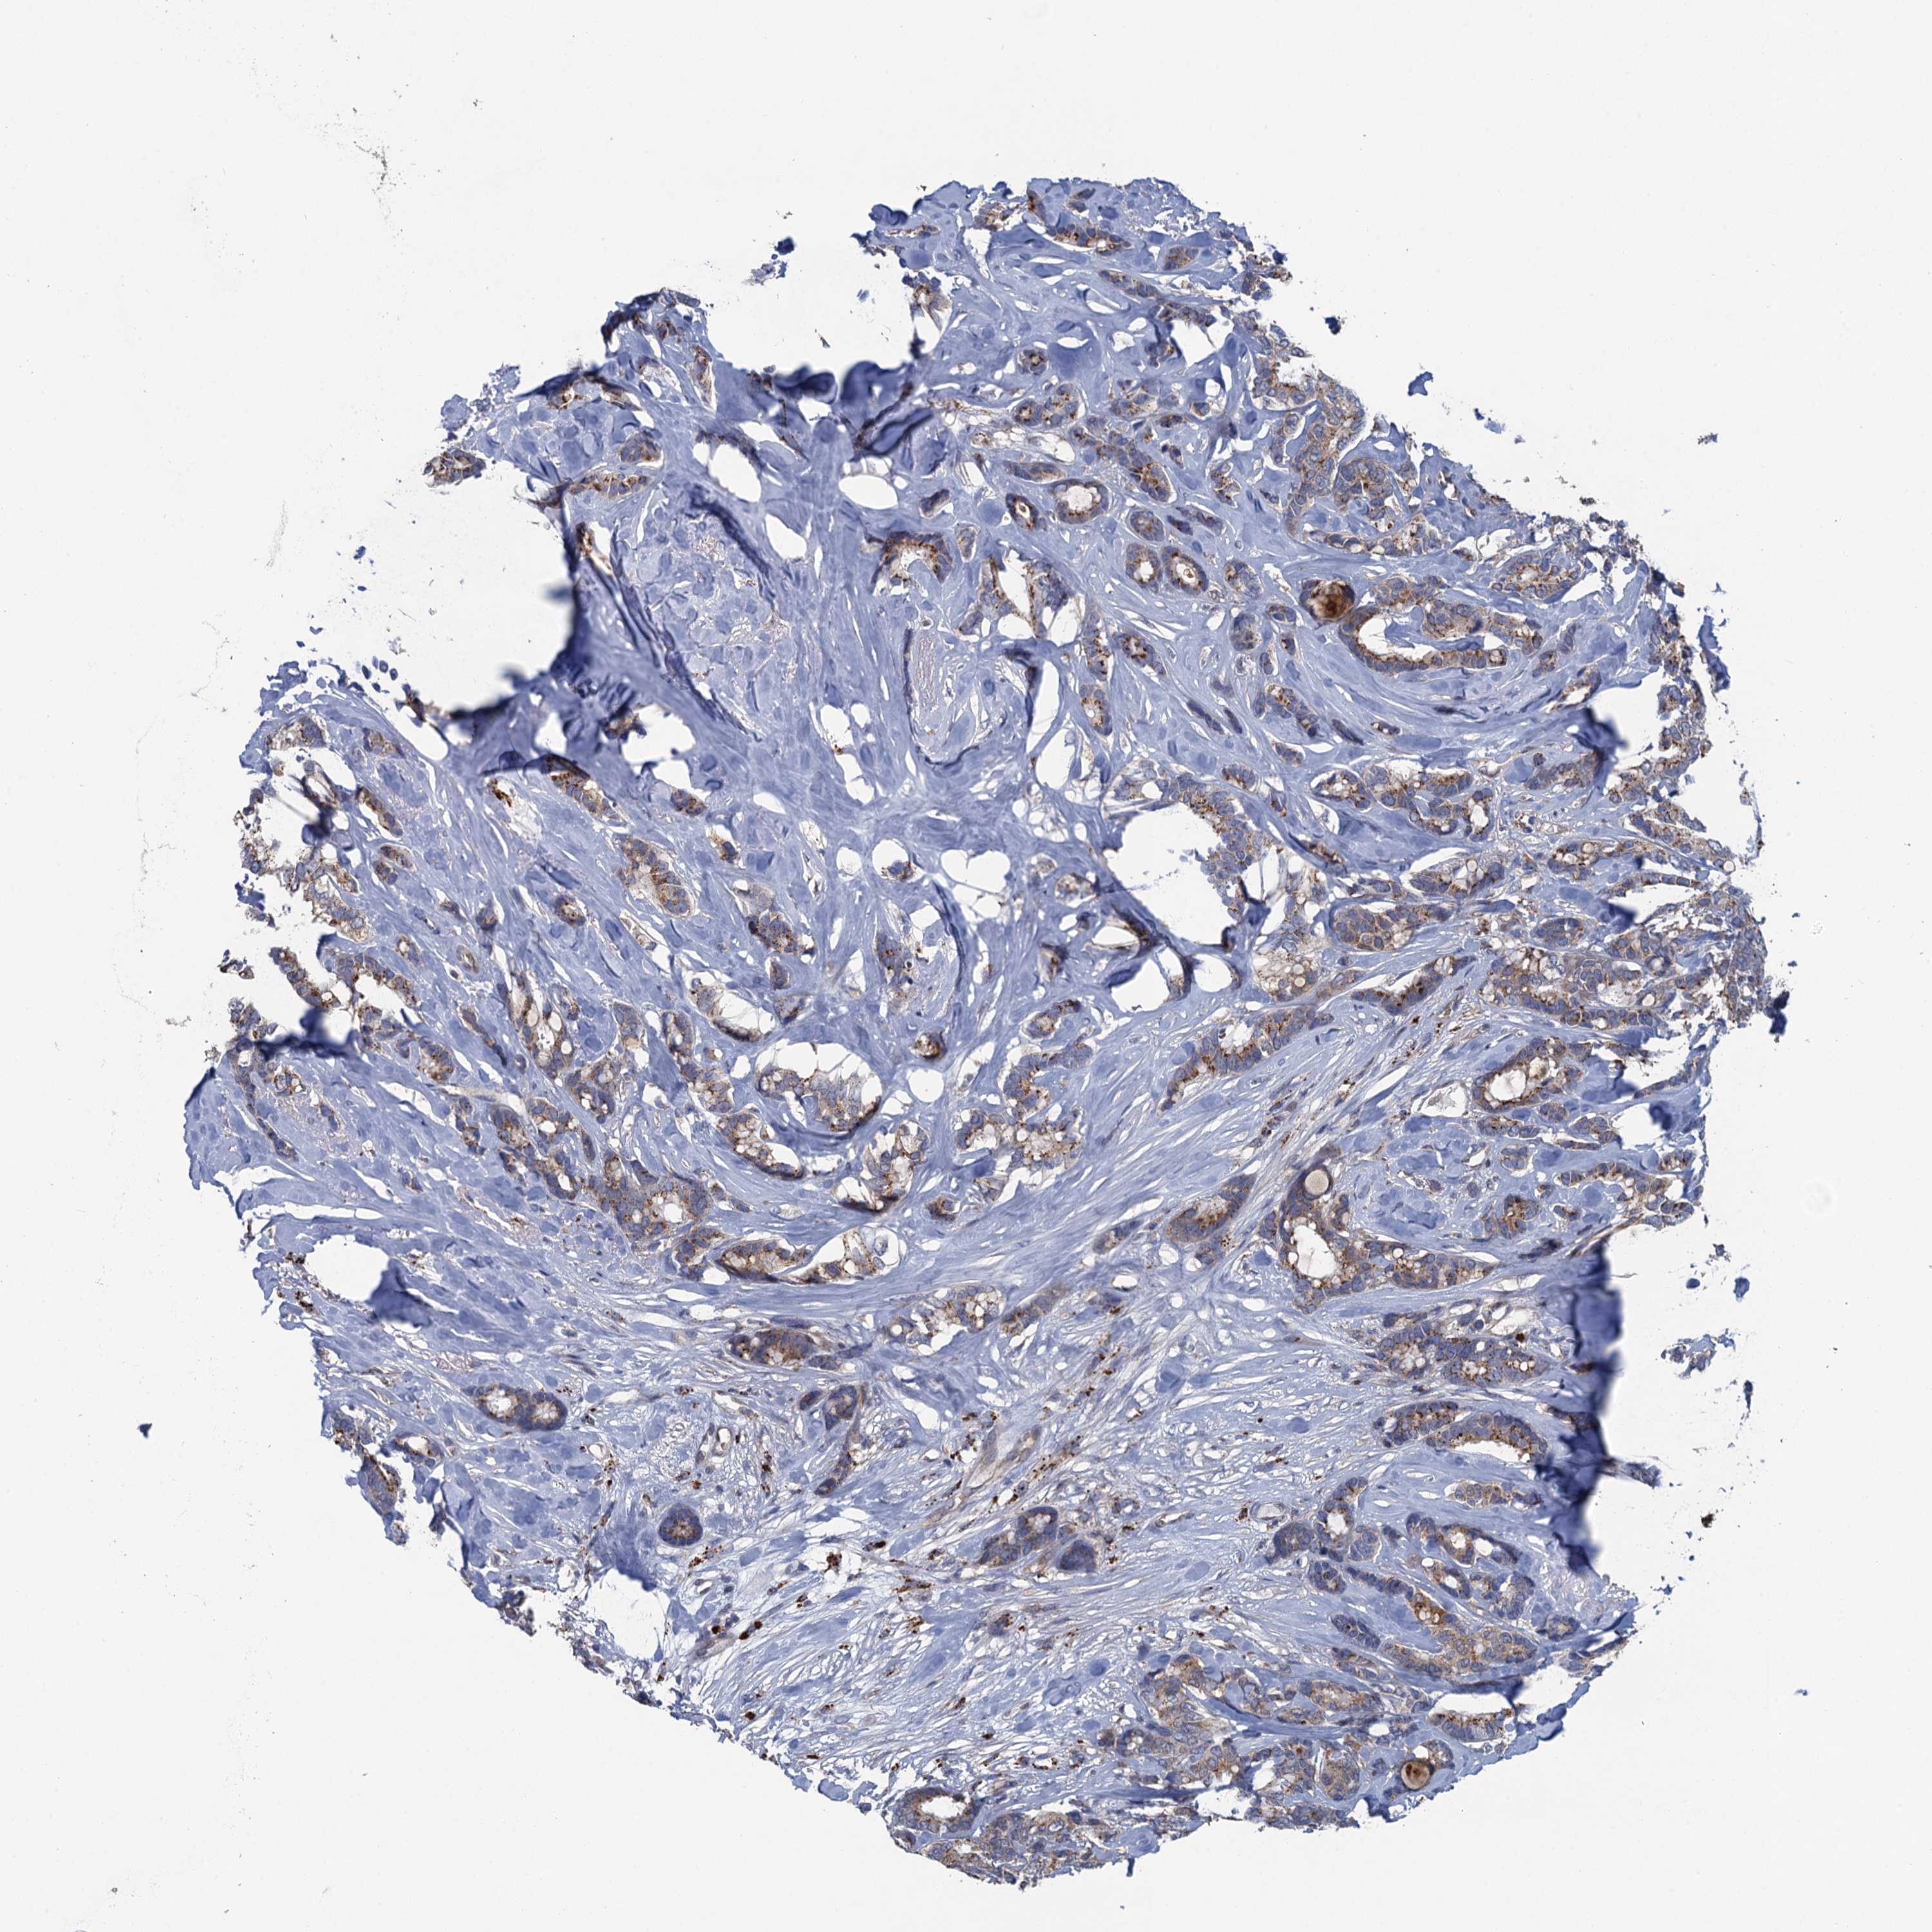

CANCER BREAST CANCER Show tissue menu

BRCA TCGA BRCA VALIDATION PROTEIN EXPRESSION